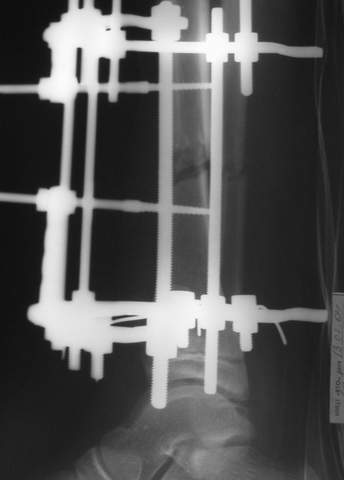

Под рукой прилагаемый пример. Как видите, "стриптиз-аппарат" (шутка проф. З.К.Башурова): 3 кольца-2 кольца-2 полукольца. В случае, который представил Евгений, характер повреждения позволил бы сразу использовать аппарат на основе 2 колец; в крайнем случае прокс. опора м.б. демонтирована сразу после репозиции.

В аттачтах №№ 1 и 2 - примеры, когда 2 кольца не позволили послеоперационно

исправить смещение фрагментов большеберцовой (по ширине и вальгусное).

1

1a

2

3a

3b

3c

В аттачте № 3 - один из примеров полукольцевого аппарат...

Это уже я баловался.

Итог? Работы больше (по времени и

интраоп "подгонке"), срастается также, а особого преимущества по сравнению с

"чиста" кольцевым (вес, удобство ношения и пр.) - я, по крайней мере,

не нашел.

Теперь не балуюсь.